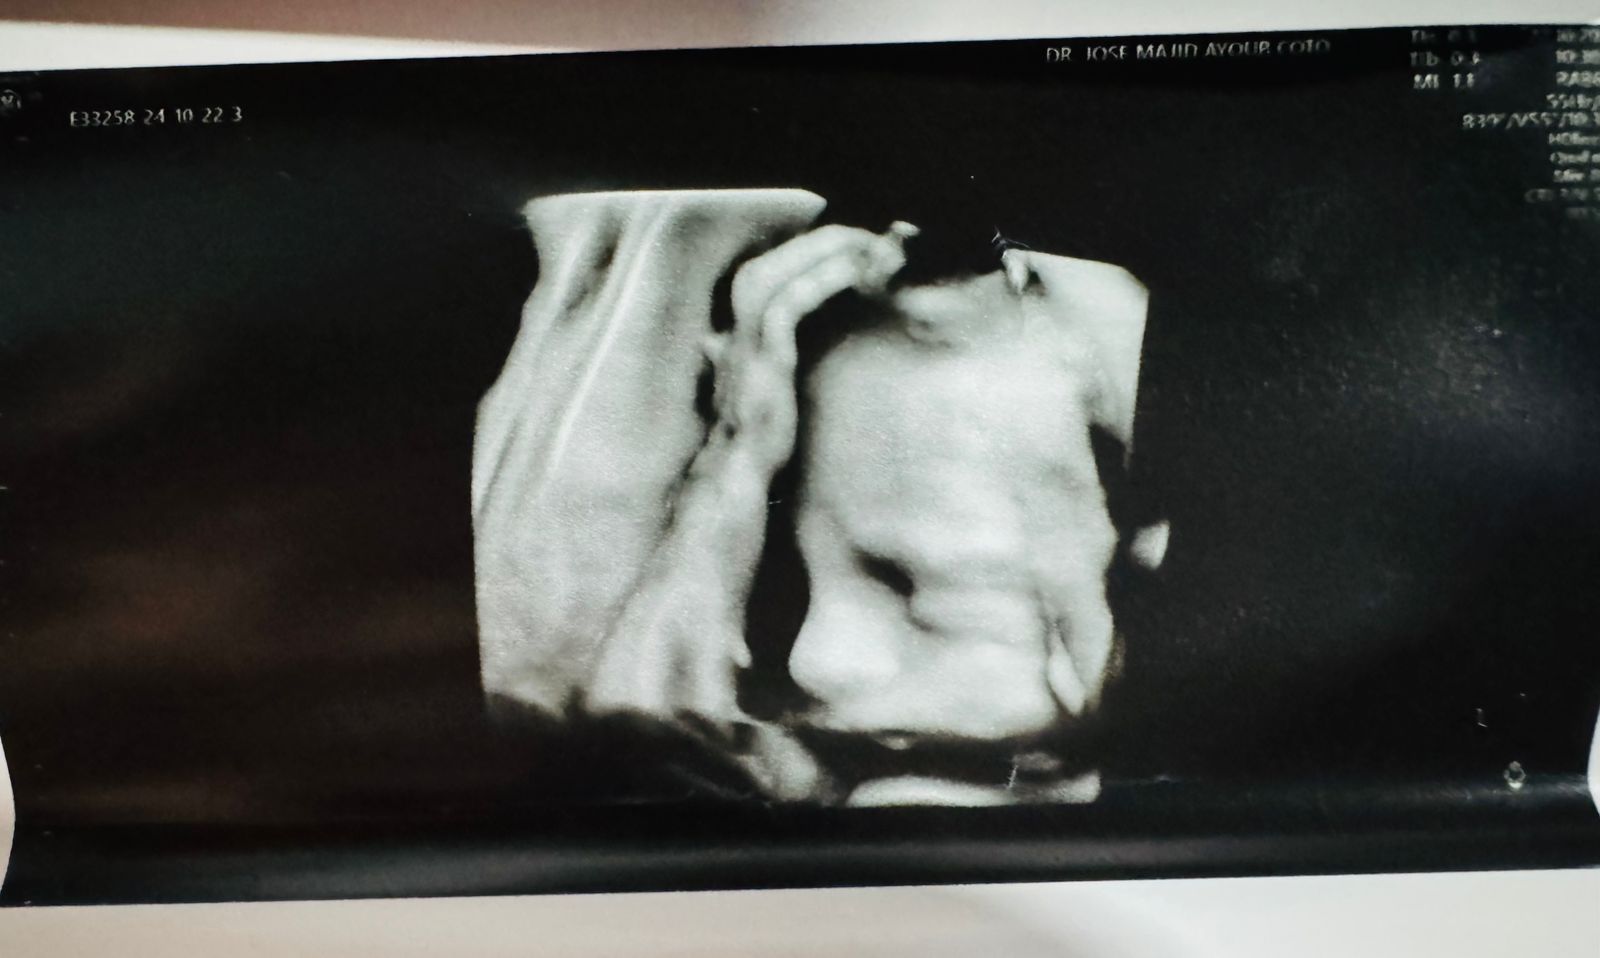

Lucas Alejandro

Mi felicidad pesa un poco mas de tres kilos.

mi pequeño corazon eres para nosotros el sol, la luna y estrellas.

Montserrat Torrero Varela

Jesus Alejandro Pereda Herrera